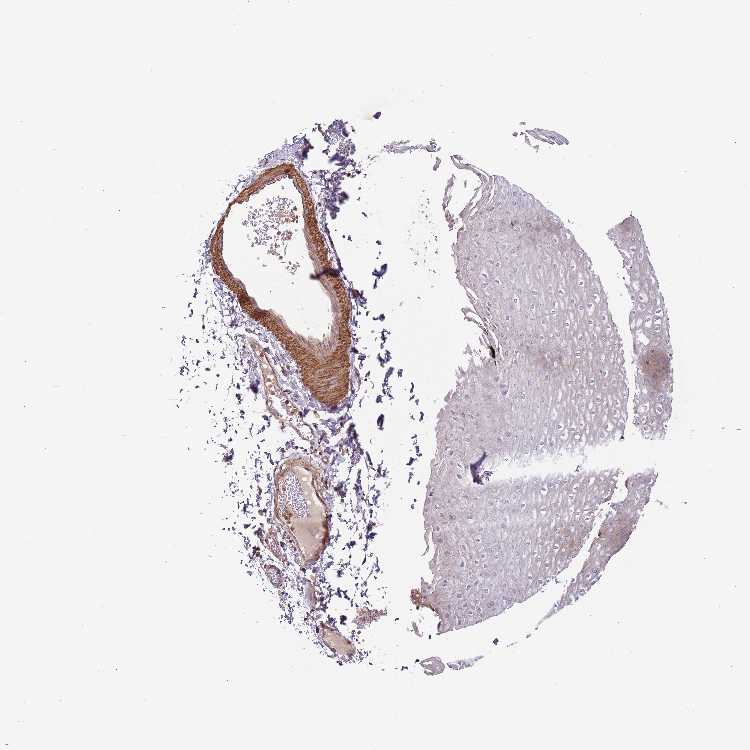

ESOPHAGUS - Antibody stainingi

Antibody staining in the annotated cell types in the current human tissue is reported as not detected, low, medium, or high, based on conventional immunohistochemistry profiling in selected tissues. This score is based on the combination of the staining intensity and fraction of stained cells.

Each image is clickable and will lead to virtual microscopy that enables deeper exploration of all samples and also displays staining intensity scores, fraction scores and subcellular localization as well as patient and tissue information for each sample.

Antibody HPA010574

Squamous epithelial cells Not detected